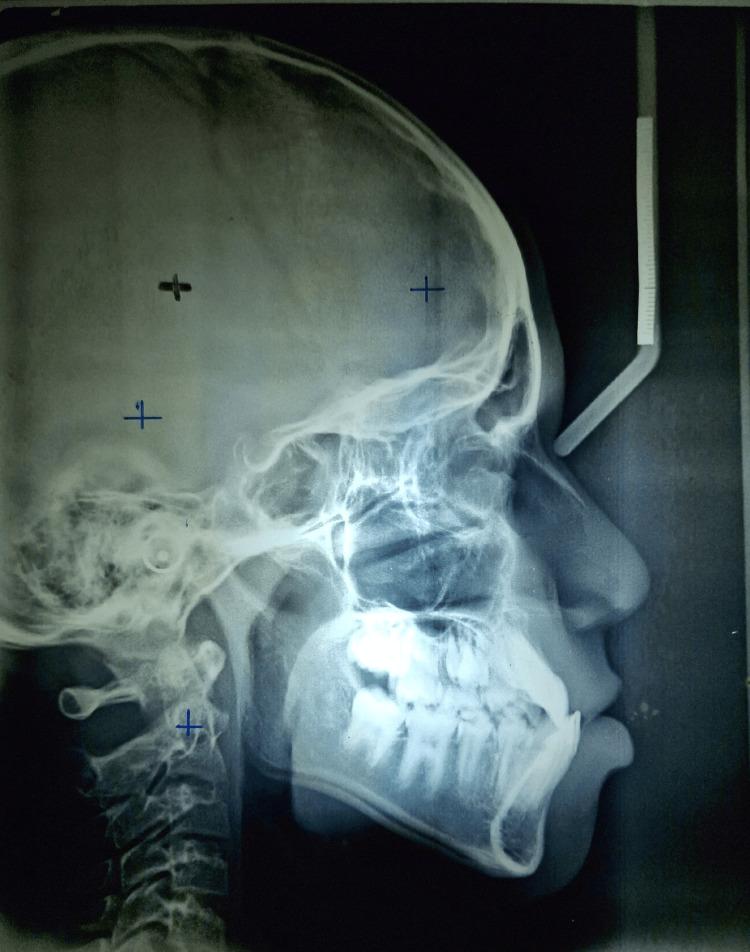

使用颏兜疗法对Ⅲ类错牙合伴前牙反牙合进行早期干预:病例报告

The Early Intervention of a Class III Malocclusion With an Anterior Crossbite Using Chincup Therapy: A Case Report.

Class III malocclusions with anterior crossbites pose significant challenges in orthodontic treatment, especially in growing children. This case report details the early intervention of a 12-year-old patient presenting with a Class III malocclusion characterized by an anterior crossbite and mandibular prognathism. A chincup was employed to inhibit mandibular growth and encourage maxillary development. Consistent use of the chincup, with regular follow-ups and adjustments, led to significant improvements. The anterior crossbite was corrected, resulting in a Class I molar relationship and an improved facial profile. The maxillary arch perimeter increased, providing space for the eruption of canines and premolars. This case demonstrates that early intervention with a chincup can effectively manage Class III malocclusion with an anterior crossbite, highlighting the importance of timely orthodontic assessment and treatment to achieve stable, long-term results.

摘要

伴有前牙反合的III类错颌畸形在正畸治疗中带来重大挑战,尤其是在生长发育期的儿童中。本病例报告详细介绍了一名12岁患有III类错颌畸形患者的早期干预情况,其特征为前牙反合和下颌前突。使用颏兜来抑制下颌生长并促进上颌发育。持续使用颏兜并定期随访和调整,带来了显著改善。前牙反合得到纠正,形成了I类磨牙关系并改善了面部轮廓。上颌牙弓周长增加,为尖牙和前磨牙的萌出提供了空间。本病例表明,早期使用颏兜干预可有效治疗伴有前牙反合的III类错颌畸形,凸显了及时进行正畸评估和治疗以获得稳定长期效果的重要性。